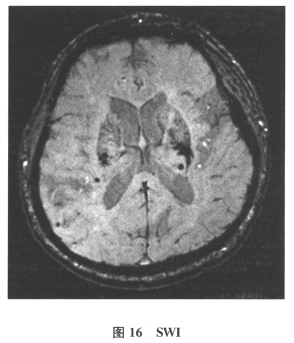

[多选题]患者男,61岁。因“发作性头晕2年,加重伴记忆力下降、走路不稳3月余”就诊。查体:BP140/70mmHg;意识清楚,构音障碍,近期记忆力及远期记忆力

[单选题]患者男,61岁。因“发作性头晕2年,加重伴记忆力下降、走路不稳3月余”就诊。查体:BP140/70mmHg;意识清楚,构音障碍,近期记忆力及远期记忆力